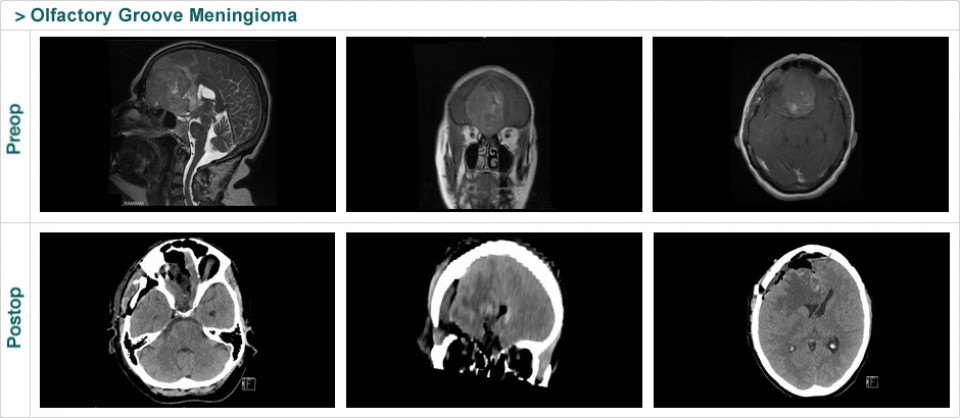

Dr. Attia is an attending neurosurgeon and the director of skull base surgery service in the department of neurosurgery at Sheba Medical Center in Tel HaShomer. His specialty focuses on skull base and cerebrovascular neurosurgery.